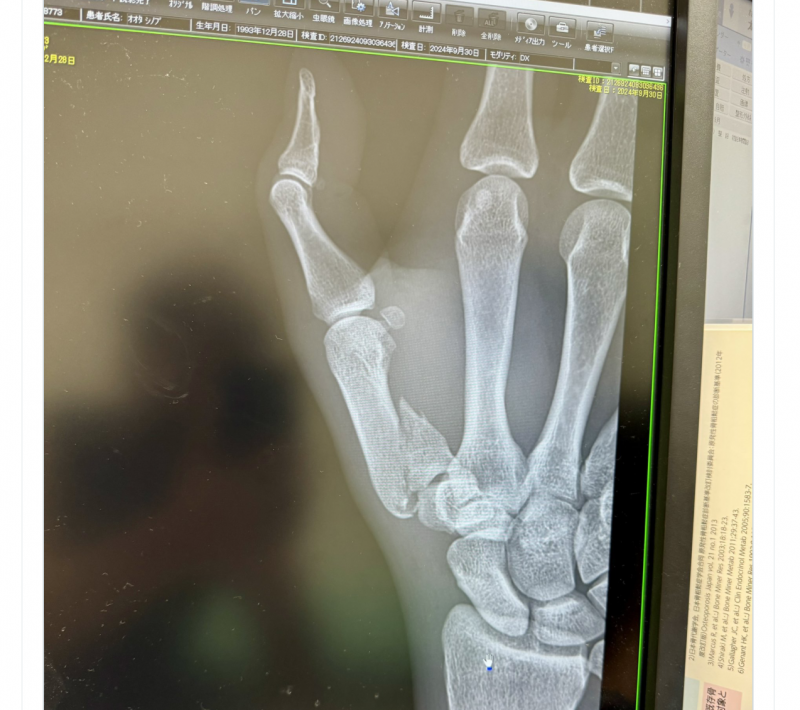

右手親指が骨折!太田のXより

この写真の記事へ